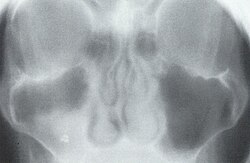

Die Röntgentomographie (auch Verwischungstomographie) ist ein historisches bildgebendes Verfahren zur Darstellung einer Schicht innerhalb des untersuchten Objekts.

Während der Belichtung werden der Röntgenfilm und die Strahlenquelle gegenläufig bewegt. Dadurch entsteht eine scharfe Abbildung nur der Strukturen, die in der Fokusebene liegen. Strukturen außerhalb der Fokusebene werden verwischt.